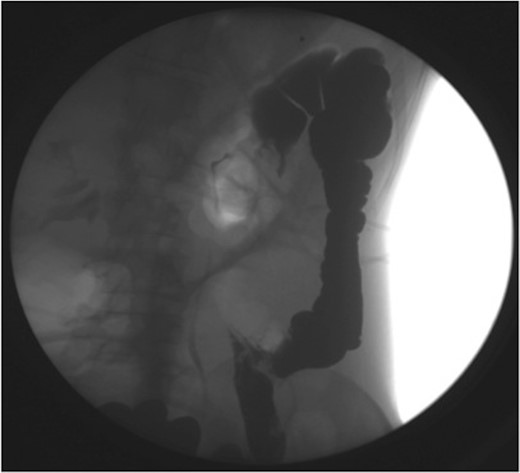

Haemoglobin was 12.6 g/dl and a WCC of 8.3 × 109/l. Other remarkable laboratory tests included a CRP of 19 mg/l. Urinalysis was normal. The AXR revealed a grossly distended large bowel. A CT scan of the abdomen revealed that the rectum, sigmoid and descending colon were collapsed with an apparent calibre change within the transverse colon with no mass lesion (Fig. 3).

CT of the abdomen (Case 2) showing a calibre change within the transverse colon with no mass lesion.